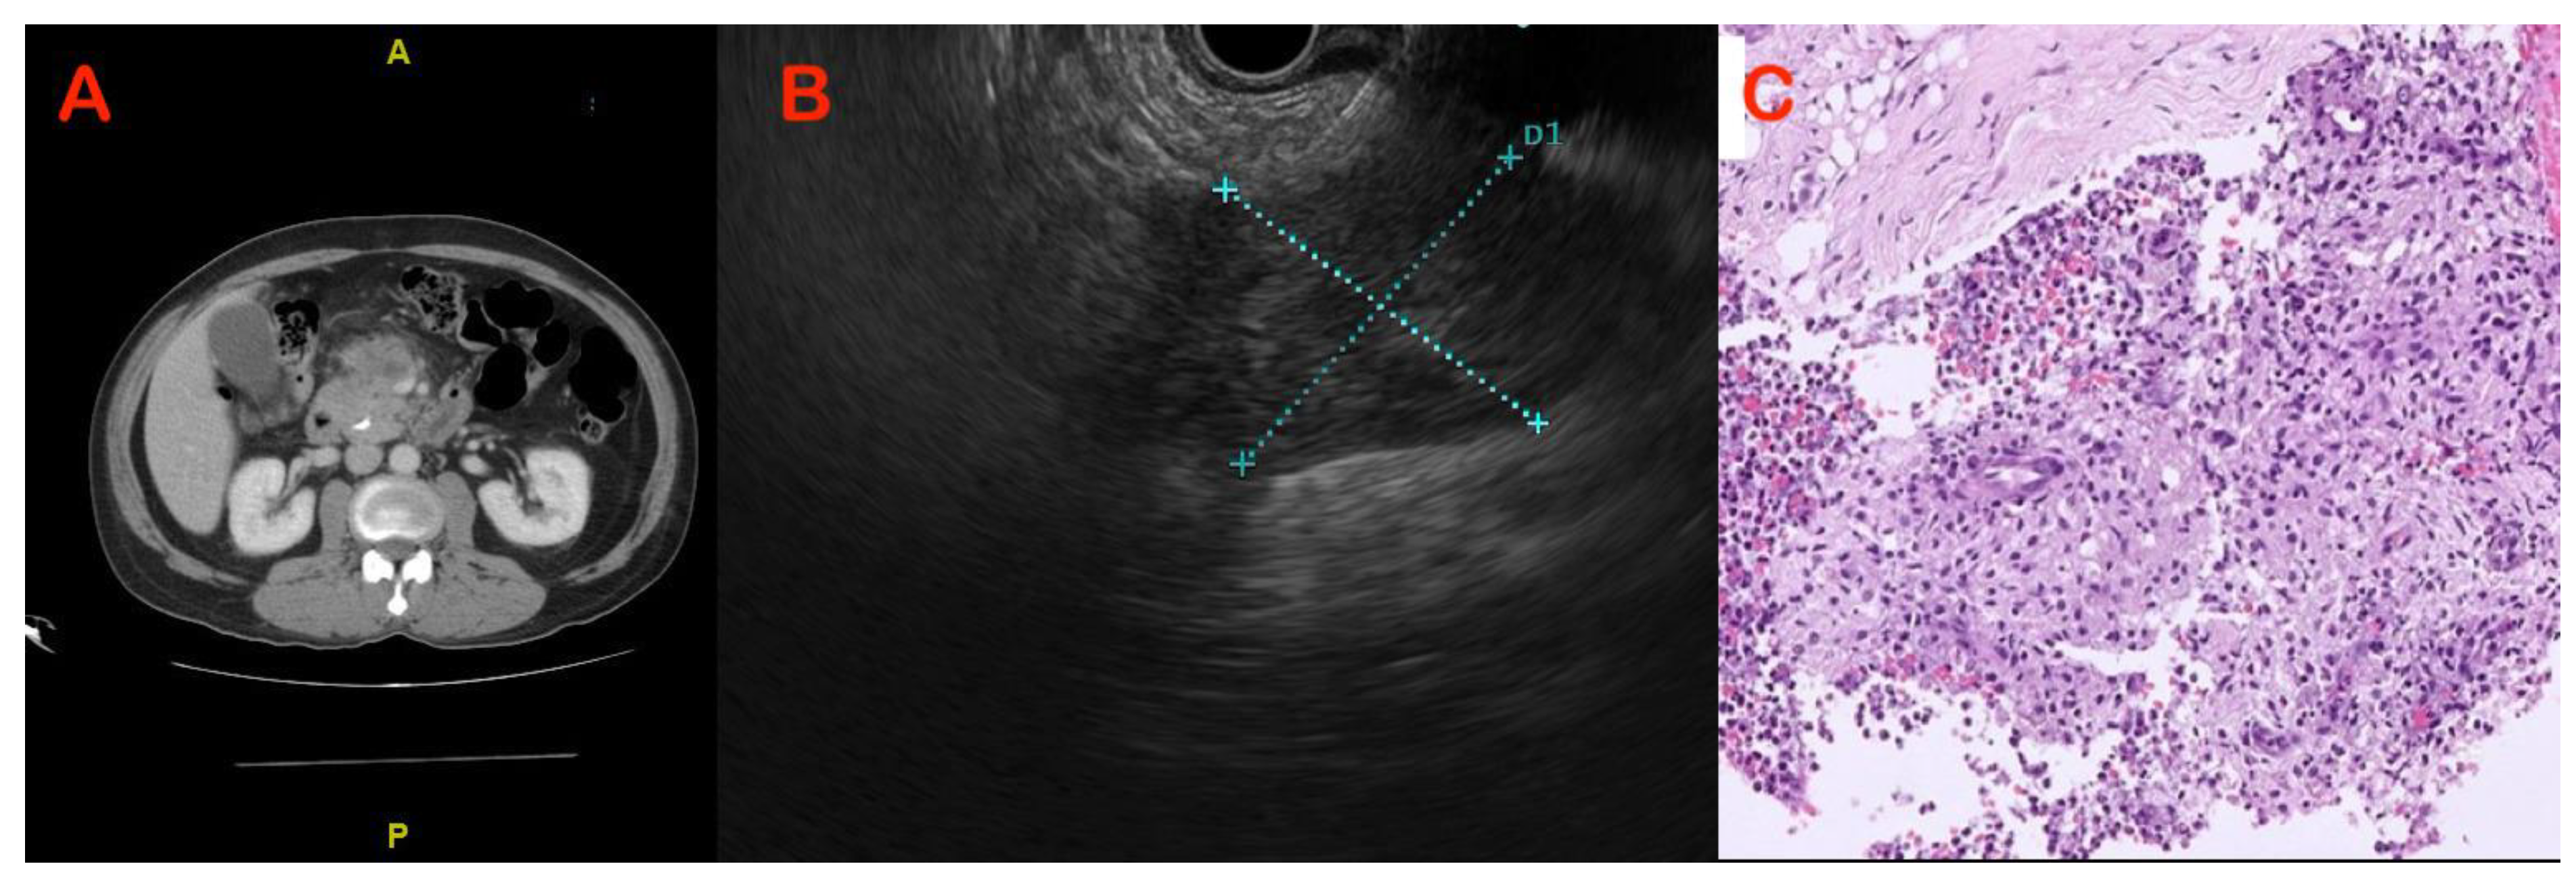

5.2. Imaging Features to Differentiate CP from PDAC

5.3. Endoscopic Modalities